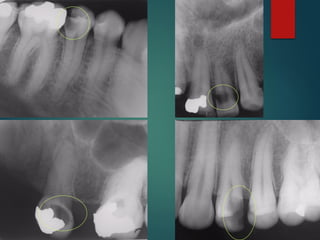

Clasificación Radiográfica

De Las Caries

Incipiente de esmalte

De esmalte

Dentinaria superficial

Dentinaria profunda

Sobreproyectada en cámara pulpar

Penetrante

 Incipiente de esmalte

 De esmalte

 Dentinaria superficial

 Dentinaria profunda

 Sobreproyectada en cámara

pulpar

 Penetrante

Diagnostico Radiografico de Caries